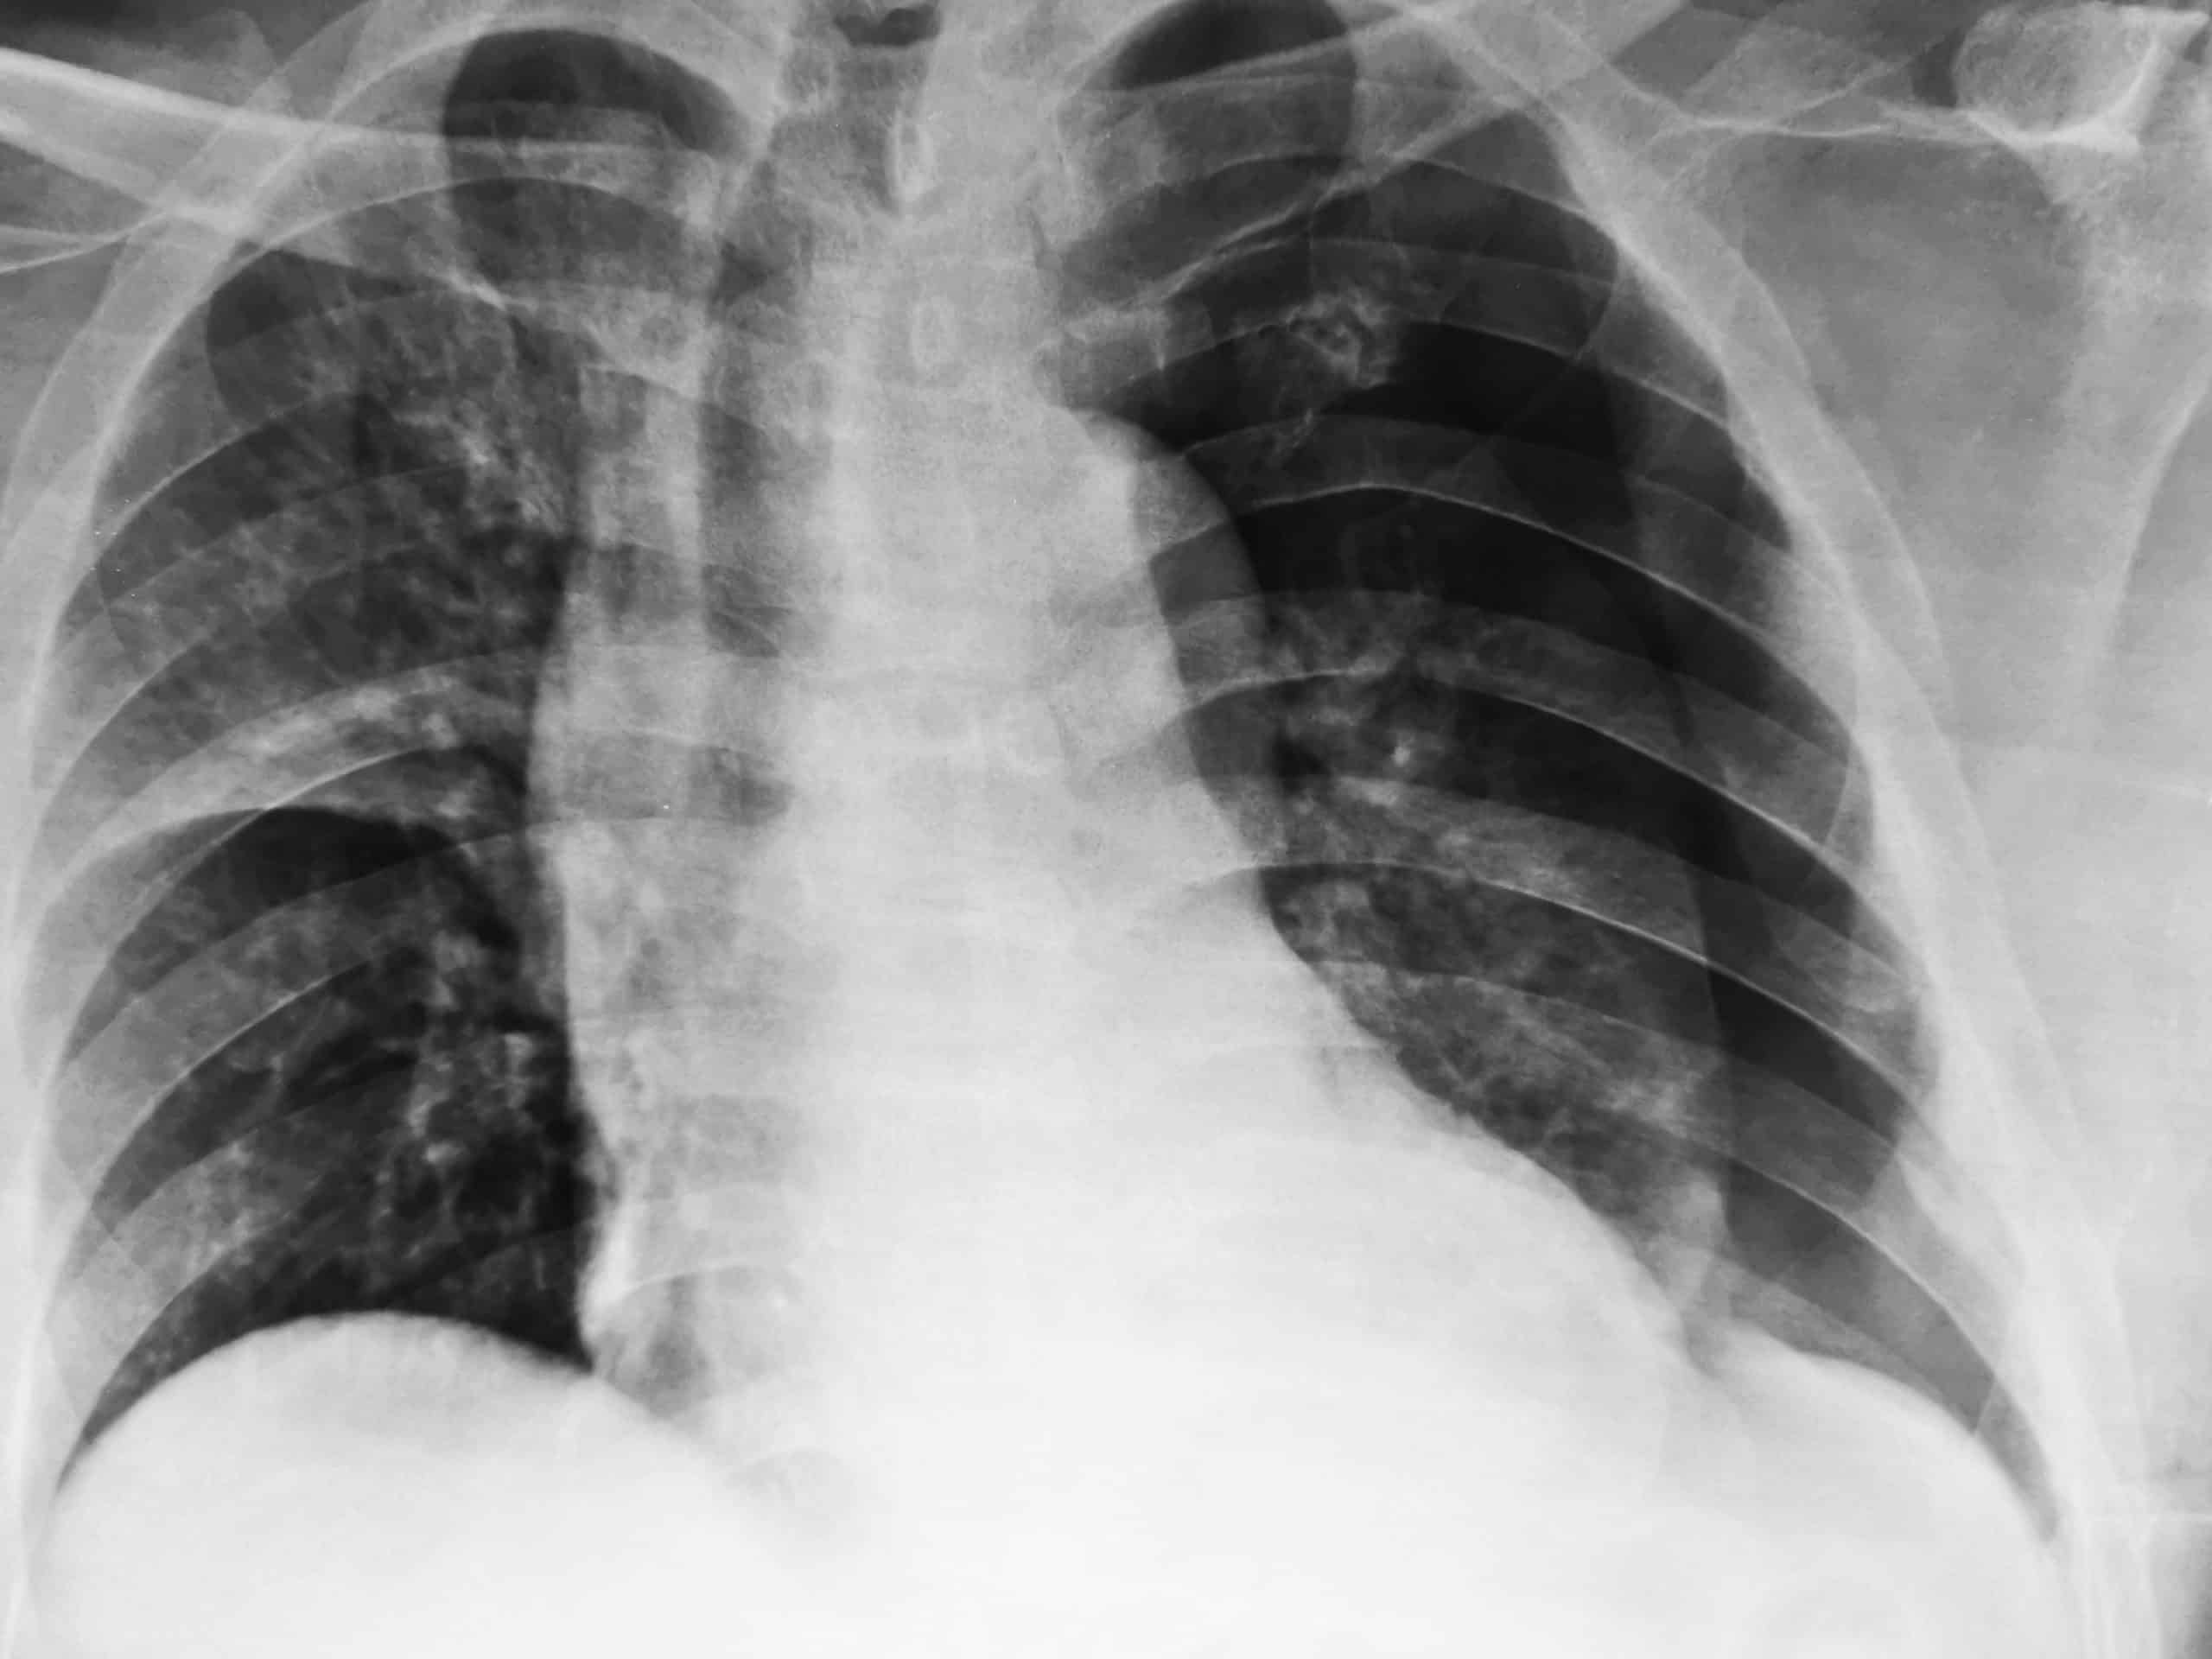

How To Read A Pneumothorax X Ray . The two lungs meet in the middle at the posterior. Identify when pleura is abnormal and the key. The lungs can be seen to reach the inner edge of the thoracic wall (arrows). This is difficult to see because the lung itself is. Recognition of a pneumothorax depends on the volume of air in the pleural space and the position of the body. On a supine radiograph a pneumothorax can be subtle. After graduating ucsf medical school, we’ve accumulated a lot of knowledge over the. A pneumothorax is seen as a region of lucency (dark) around the edge of the lung. In this video, you'll learn how to identify when radiological pleura is abnormal and the key.